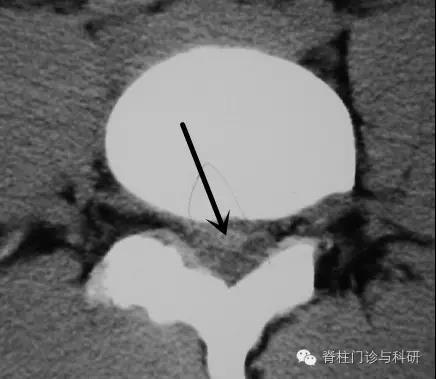

而下图这类患者,游离的髓核与神经根位置上有处于焦灼不清的倾向,短期内“自愈”的可能小些。但突出物CT值不高,为单纯的髓核组织,系统保守治疗或能为其部分蠕化、溶解、吸收创造条件。